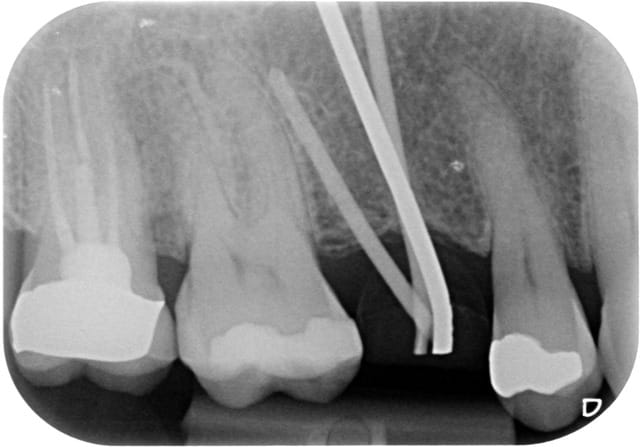

Patient de 33 ans venant pour une molaire douloureuse...

Je pense tenir le record du n'importe quoi implantaire.

Pourtant les endos ne sont pas immondes

euh 37 et 16 y a comme un problème